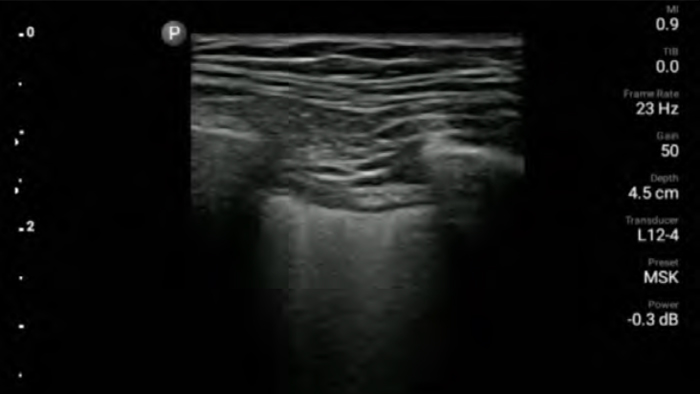

Reduce complications

in needle guided procedures

Lumify handheld ultrasound for anesthesiology helps you clearly visualize border definition with your needle placement, surrounding nerves, vessels and fascial planes.

Lumify helps you clearly visualize needle placement, surrounding nerves, vessels and fascial planes.